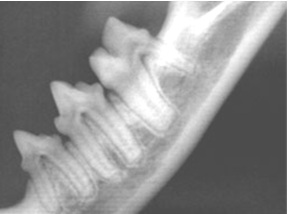

Dog and Cat Normal Dental X-Rays

X-Rays on Left -- Tooth supporting bone is normal in appearance